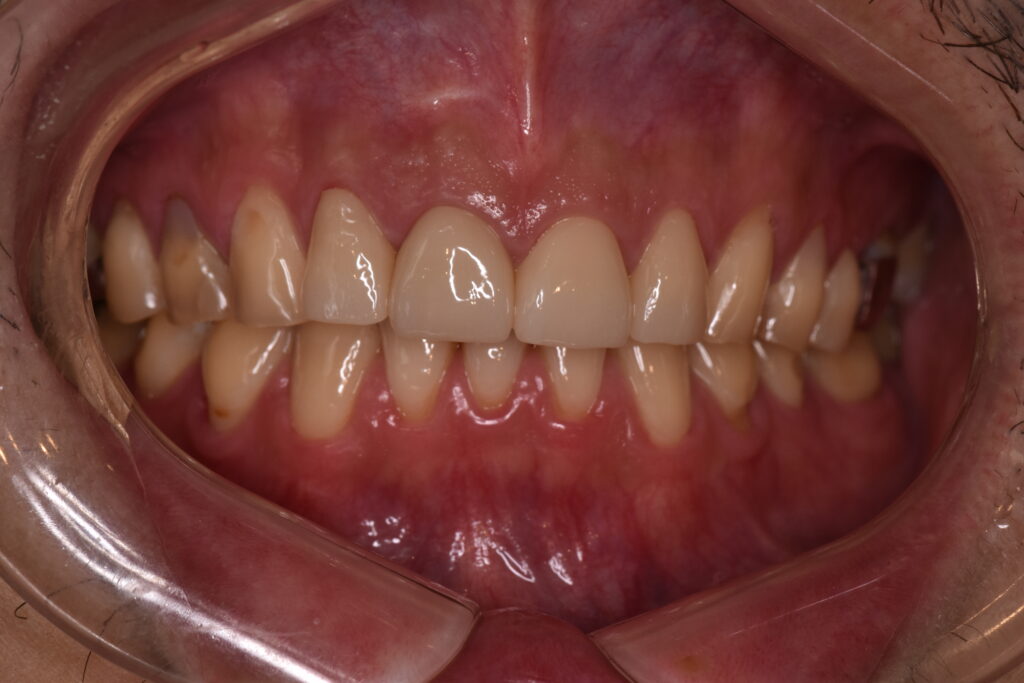

【処置後】